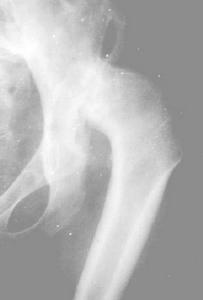

診斷主要根據病史,臨床症狀及體徵,在疑有血源性化膿性關節炎病人,應作血液及關節液細菌培養及藥物敏感試驗。X線檢查在早期幫助不大,僅見關節腫脹;稍晚可有骨質脫鈣,因軟骨及骨質破壞而有關節間隙狹窄,晚期可發生關節骨性或纖維強硬及畸形等,有新骨增生現象,但死骨形成較少。化膿性關節炎應與急性化膿性骨髓炎、風濕性關節炎、結核性關節炎以及類風濕性關節炎相區別。1、90%為單關節炎,成人多累及膝關節,兒童多累及髖關節,其次為踝、肘、腕和肩關節,手足小關節罕見。

2、關節紅、腫、熱、痛,壓痛明顯,活動受限。深部關節如髖關節感染時,局部腫脹、疼痛,但紅熱不明顯。

關節周圍軟組織腫脹影,骨質疏鬆,以後關節間隙變窄,骨盾破壞,反應發現有質增生。晚期關節呈纖維性或骨性融合,死骨形成,關節脫位或間脫位。X線檢查時,在早期由於關節液增加而關節囊腫脹,間隙增寬,骨端逐漸有脫鈣現象。如關節面軟骨有破壞,則關節間隙變窄。有時可講發骨骺滑脫或病理性脫位。較晚期,關節面下骨質呈反應性增生,骨質硬化,密度增加。最後關節軟骨完全溶解,關節間隙消失,呈骨性或纖維性強直,或餅發病理性脫位。其X線表現為:

1. 早期關節內有化膿性炎症時,關節周圍軟組織常有充血及水腫,表現為軟組織厚於健側,層次不清。關節囊因關節內積液而膨脹,脂肪層被推移呈弧形。偶爾可見關節間隙輕微增寬,應與健側對照,才不會漏診。

2.關節間隙狹窄化膿性細菌進入關節後首先引起的滑膜炎。滲出液內含有大量中性白細胞。白細胞死亡後所釋放出的大量溶蛋白酶、很快地溶解關節軟骨。根據關節軟骨被破壞的程度,常於發病後短期內出現關節間隙狹窄,甚至完全消失。

3.關節面改變關節軟骨被破壞後,即可進一步破壞軟骨下骨質。最早出現在關節面的相互接觸部分,即負重部分。表現為關節面模糊和不規則。繼而形成較大的破壞區,形成死骨。由於機體的修復作用,破壞區周圍因骨質增生而密度增大,關節邊緣有唇樣骨質增生。當骨小梁貫穿關節間隙以聯接兩側骨關節面時稱之骨性強直。

4.關節軟骨及骨質破壞嚴重時可引起脫位或半脫位一般青少年和成人,常因關節軟骨破壞形成骨性強宜,而兒童多發生骨端的破壞,吸收,引起病理性脫位。